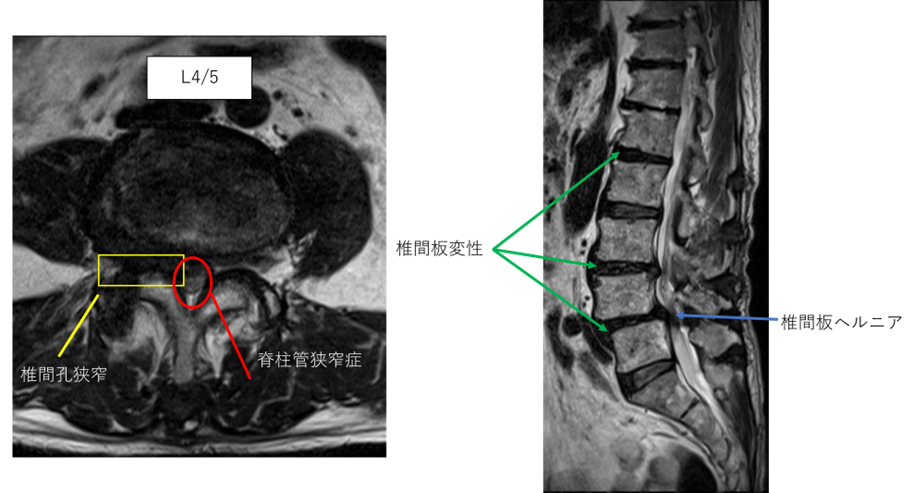

L1/2: 椎間板変性症

L2/3: 異常なし

L3/4: 椎間板変性症、左椎間孔狭窄

L4/5: 椎間板変性症、椎間板ヘルニア、脊柱管狭窄症、右椎間孔狭窄

L5/S: 異常なし

以上の事が画像上認められます。

L1/2.3/4.4/5に

椎間板変性症、椎間板ヘルニア、脊柱管狭窄症、椎間孔狭窄を認め、主症状の原因の可能性が高い。